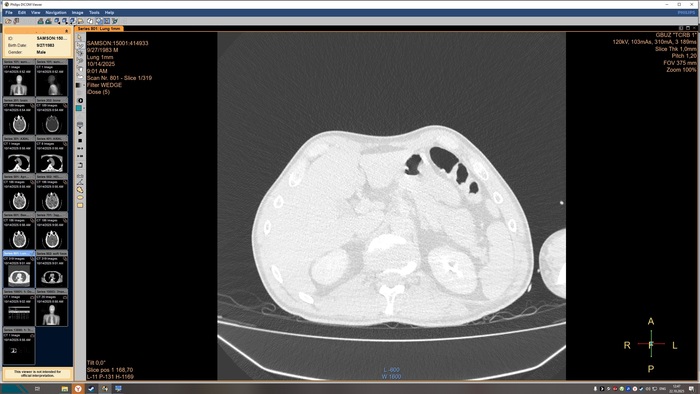

не выявлено. На прямой топограмме, серии аксиальных срезов и реконструкций получены

изображения органов грудной клетки от уровня верхней апертуры грудной клетки до уровня

задних рёберно-диафрагмальных синусов в нативном виде. Легкие в полном объёме,

пневматизация снижена. Справа в С3 выявляется бронхопневмоническая инфильтрация.

Конфигурация и просвет стволовых бронхов сохранены. Средостение обычной формы и

положения, дополнительных образований в нём не выявлено. Внутригрудные

бифуркационные и парааортальные лимфатические узлы не увеличены. Анатомия крупных

сосудов не нарушена, размеры в пределах нормы, стенки аорты и венечных артерий с очагами

кальцинатов. Плевральные утолщения и скопления жидкости отсутствуют. Диафрагма и мягкие

ткани грудной клетки без видимых патологических изменений. Признаков остеолитического, -

пластического процессов, травматических повреждений костных структур на исследованном

уровне не выявлено. ДИ по типу остеохондроза.

КТ-признаки очаговых образований головного мозга. КТ-признаки правосторонней

верхнедолевой сегментарной б/пневмонии. ДИ ГОП.

Снимки КТ